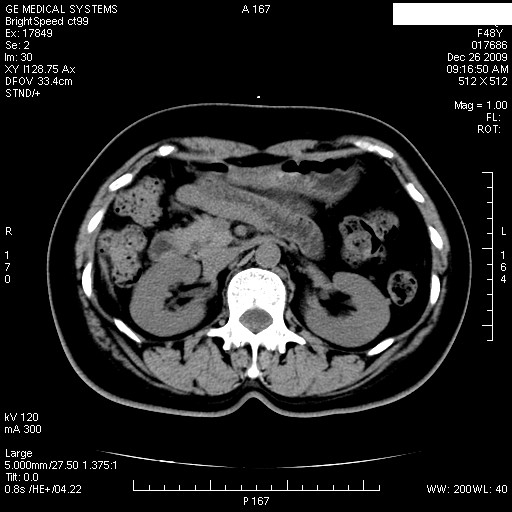

患者女性 48岁 突发上腹部疼痛,无其他不适,查体莫菲氏征阴性,ct示:胆囊炎,胆总管上端轻度扩张

图片如下:

1.图像看上去不是同一人(前组图像十二指肠未见明显异常,后组图像可见十二指肠占位)

2.后组图象印像

a.十二指肠球部前壁占位

b.坏蛆性胆囊炎,胆囊-结肠瘘(瘘口微小且时间较短,结肠内容返流入胆囊,形成胆囊壁钙化,胆囊内钙盐等沉积)

c.胆管炎,肝外胆管轻度扩张